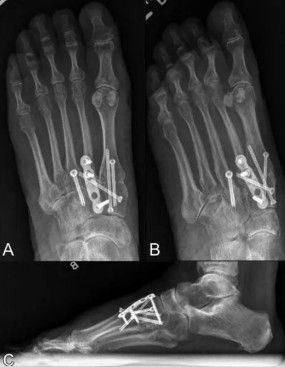

- O que é a Artrodese? É um procedimento cirúrgico que tem como objetivo fundir (unir) de forma permanente as articulações afetadas pela artrose. Ao eliminar o movimento entre os ossos, elimina-se também o atrito doloroso e a inflamação.

- Objetivo: Proporcionar um pé estável e, principalmente, sem dor, permitindo que o paciente retome suas atividades diárias com conforto.

- Como é feita: Durante a cirurgia, a cartilagem danificada é removida das superfícies ósseas das articulações. Em seguida, os ossos são posicionados corretamente e fixados com placas, parafusos ou outros implantes metálicos. Com o tempo, os ossos se consolidam (se fundem), tornando-se uma única peça óssea.

- Pós-operatório: O período de recuperação envolve um tempo de imobilização (com gesso ou bota ortopédica) para permitir a fusão óssea, seguido de fisioterapia intensiva para reabilitação e retorno gradual às atividades. A paciência e a dedicação do paciente são cruciais nessa fase.